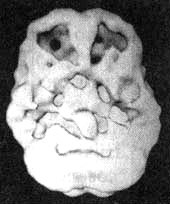

Мозг Карла. Алкогольная зависимость

Трехмерное изображение нижней поверхности. Обратите внимание, что мозг выглядит сморщенным, особенно в области префронтальной коры и височных долей.